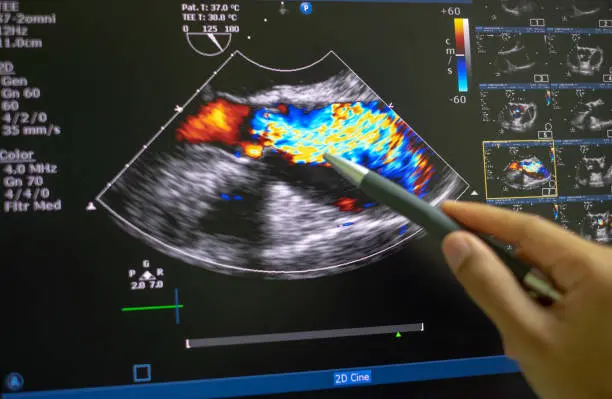

Doppler Scan

Pelvic Ultrasound Scan